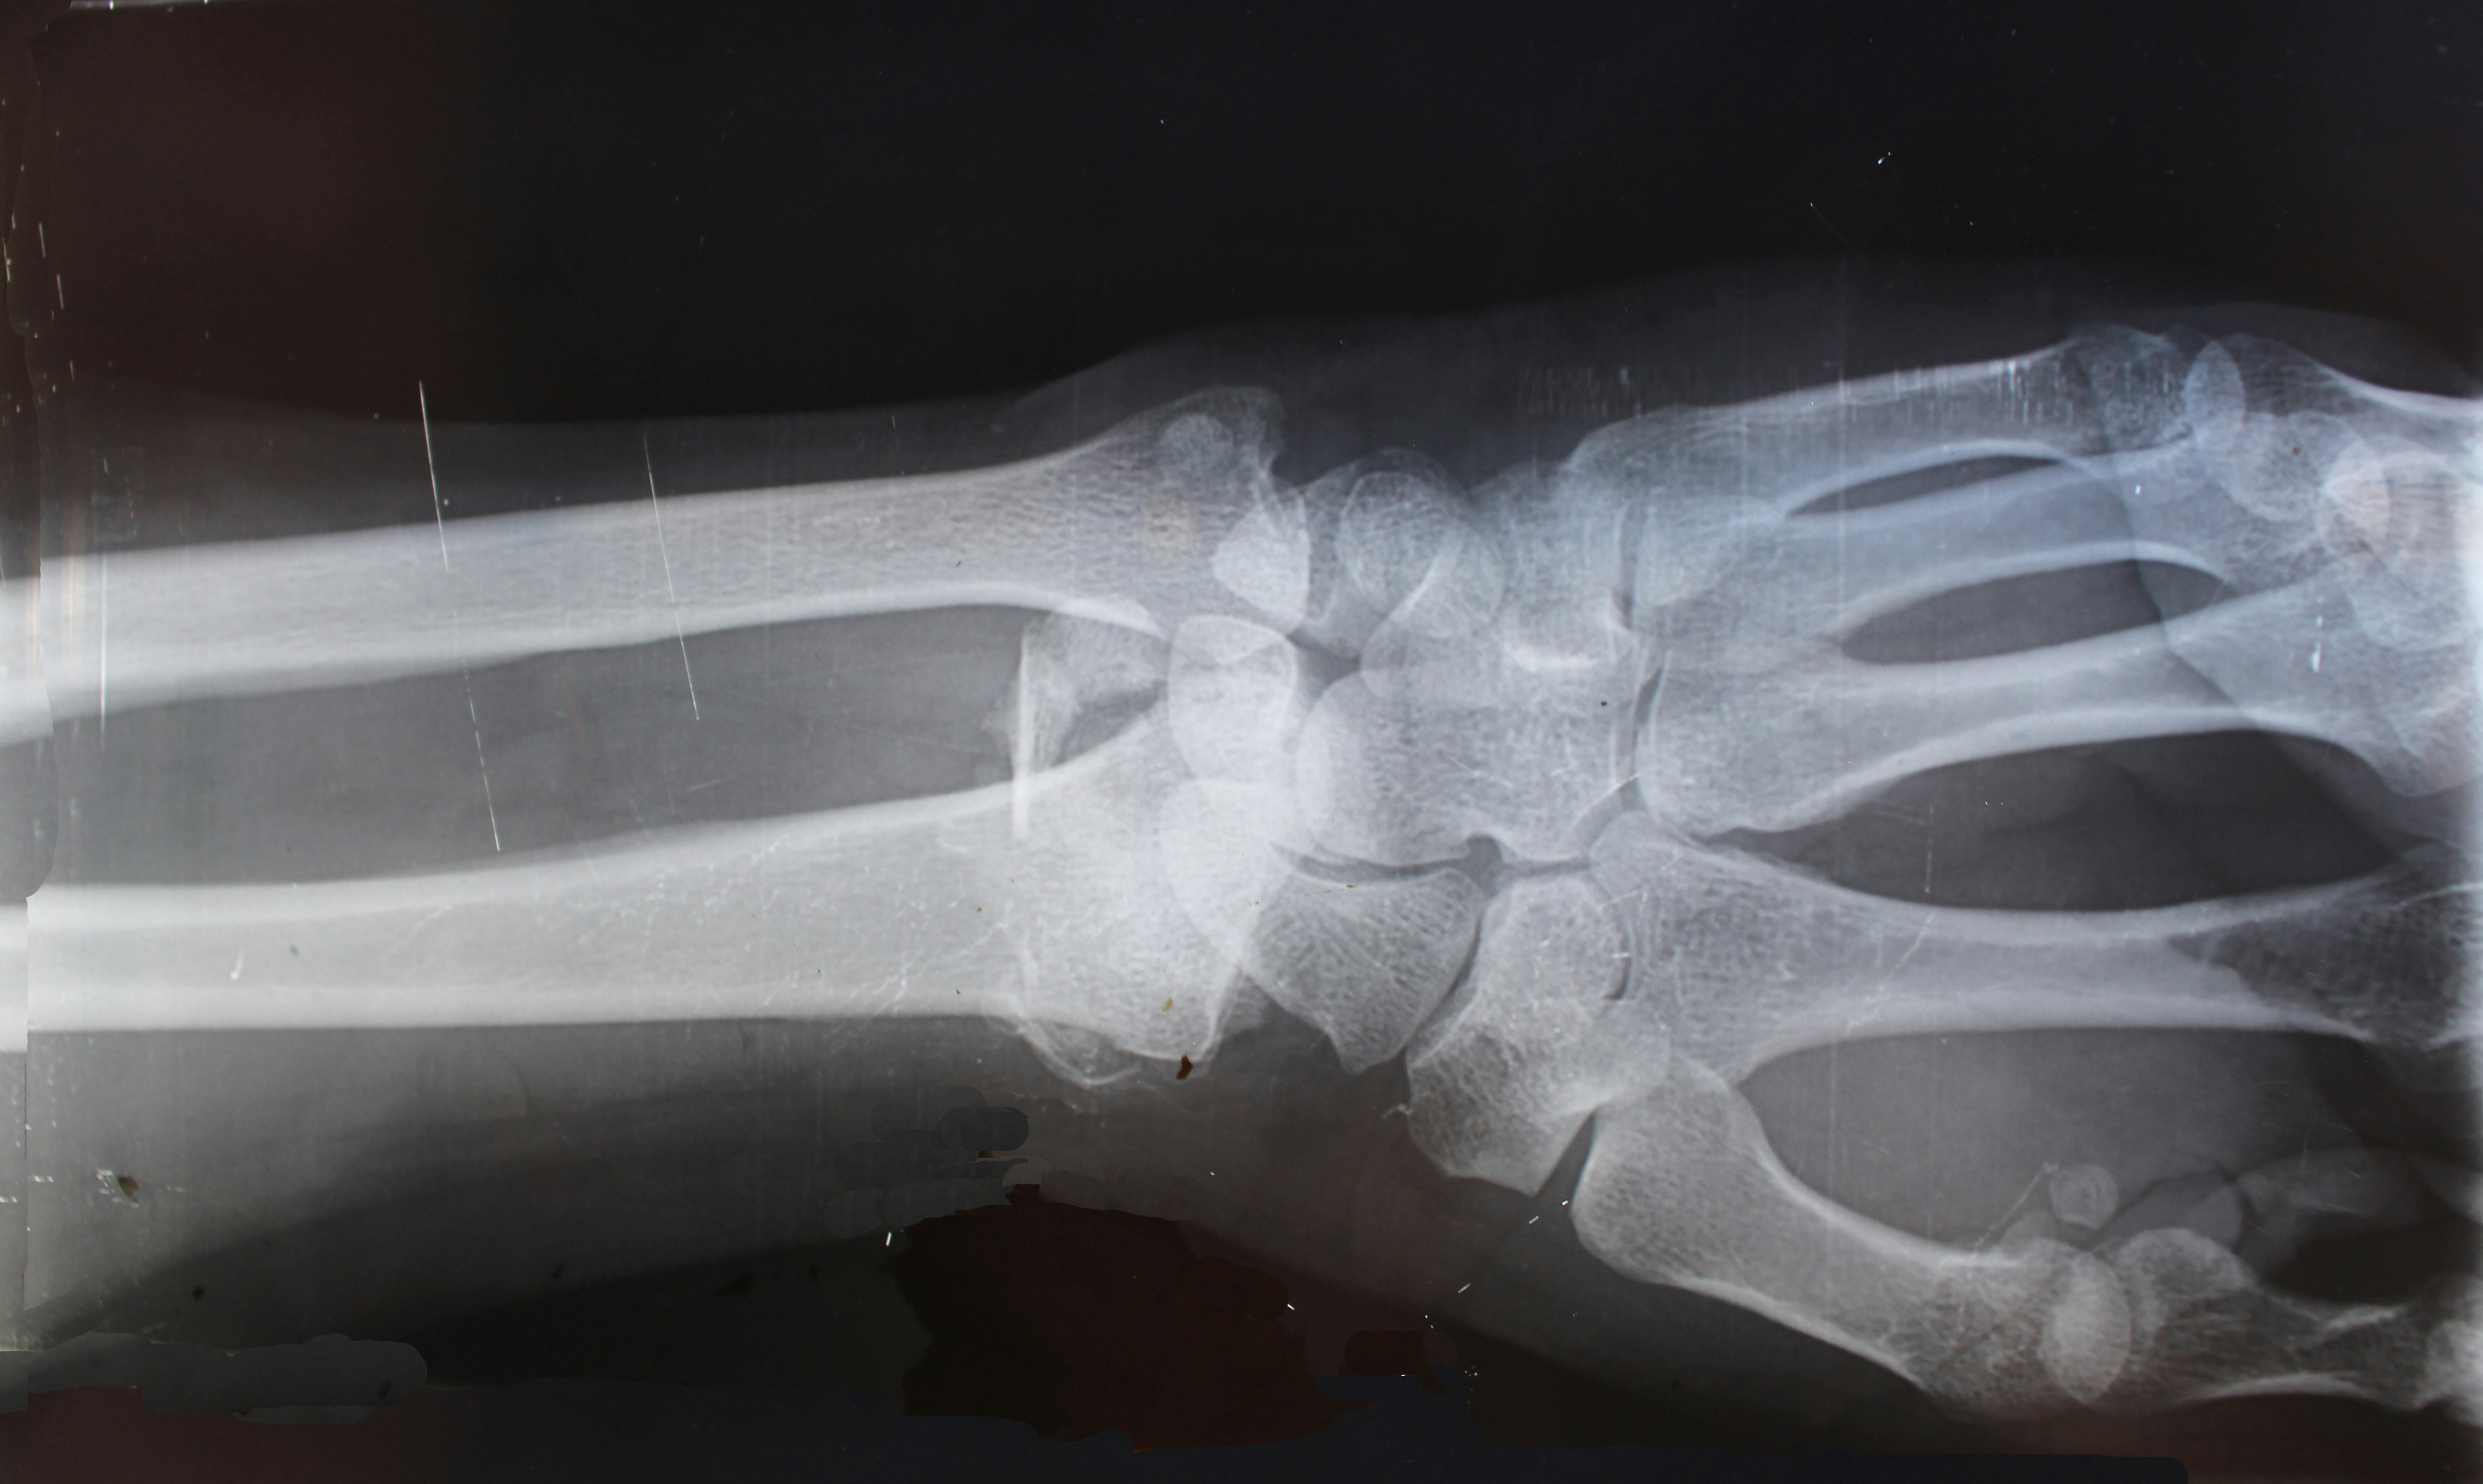

가장 흔한 원인은 무릎 관절을 보호하고 있는 **연골의 마모**입니다. 오랜 시간 관절을 사용하면서 연골이 얇아지고 뼈와 뼈가 직접 부딪히게 되는데, 이 과정에서 염증과 극심한 통증이 발생합니다. 주로 하중을 많이 받는 무릎 안쪽에 나타나며, 오랫동안 쪼그려 앉거나 무리한 동작을 반복할 때 퇴행 단계에 기여합니다.